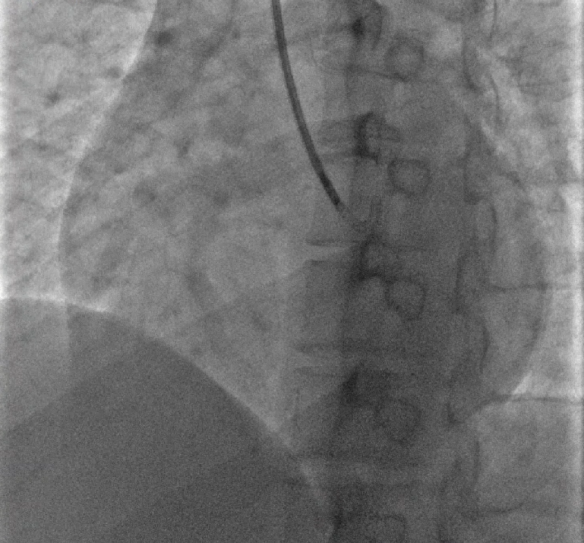

但由于患者体重为 240 多斤,心脏比正常人的都大一号,未能寻找到相匹配的心脏供体,因此心脏移植无法实施。在转入心血管内科后,病区主任、心肌病团队负责人辛辉教授迅速带领心肌病团队,针对患者病情积极查找「扩心病」的病因,考虑患者心衰的原因为「慢性炎症性心肌病」。

通过专家共同制定的个性化治疗方案,王先生的心功能明显改善,更避免了心脏移植手术,大大提高了生存质量。一个半月内,心脏射血分数由入院前的不到 30%,成功改善为 46%。